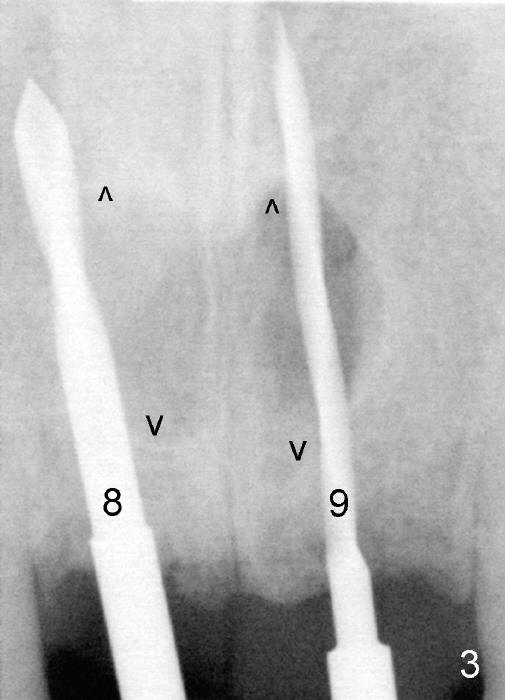

Following extraction of the two mesiodens, osteotomy starts with pilot drills (Fig.3: 8,9). As planned, these pilot drills go through two of the cortical plates of the mesiodens' sockets (arrowheads).

Trajectory is being corrected while osteotomy is increasing with reamers (Fig.4: 3 and 2.5 mm). When a 4.5x20 mm tap is inserted at the site of #8 (Fig.5), it is stable. A 3.5x20 mm tapered drill is at the site of #9 for parallelism. When the tap is removed from the osteotomy of #8, the middle portion of the 3.5x20 mm drill at the site of #9 is seen to pass the socket of the left mesiodens (Fig.6: <).

The insertion torque for the implants (4.5x20 mm and 4x20 mm) are 40 and 60 Ncm for #8 and 9, respectively (Fig.7). The stability is probably due to the fact that these two implants are engaged into the two cortical plates of the sockets (arrowheads). Allograft is placed in the mesiodens sockets. Immediate provisionals are fabricated. Fig.8,9 show the provisionals 18 days postop. One of the provisionals (#8) is dislodged 5 weeks postop. Before recementation of the provisional (Fig.10), healthy granulation tissue is found next to the implant (^).